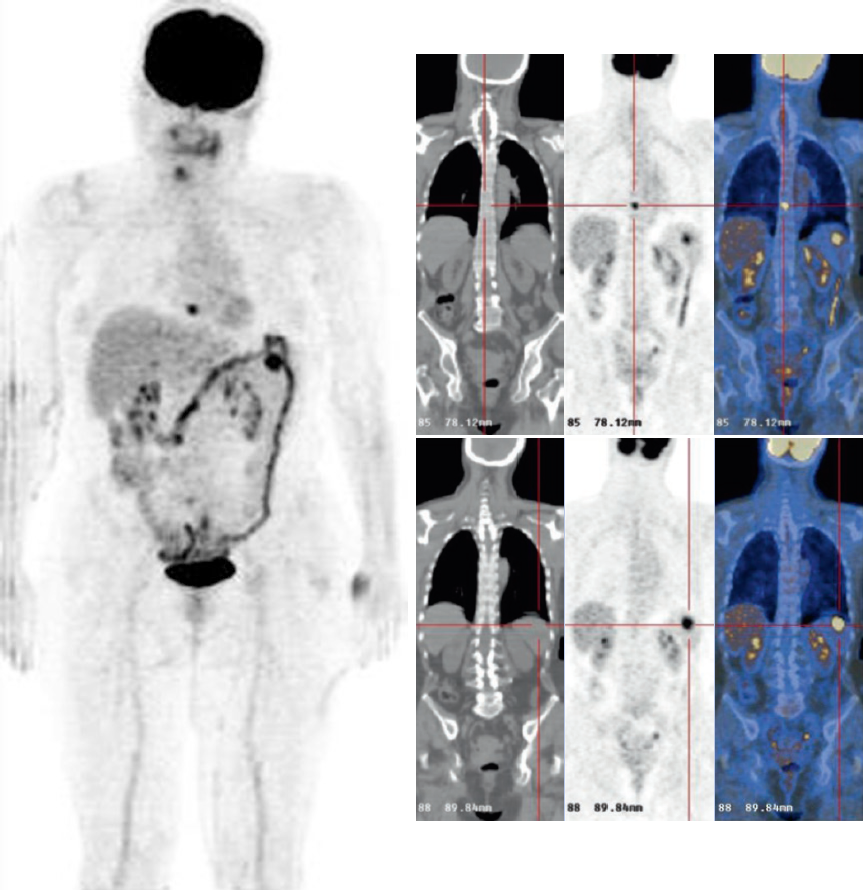

Ristadiazione di melanoma dopo immunoterapia.

Diverse aree di aumento dell’assorbimento dovute a melanoma avanzato disseminato prima (a) e dopo l’immunoterapia (b).

Il ruolo della PET-FDG per la valutazione della risposta nei pazienti trattati con immunoterapia è in fase di studio. La PET-FDG sembra essere uno strumento promettente per la valutazione precoce della risposta, la valutazione della durata della risposta al trattamento e il monitoraggio delle resistenze. Questo potrebbe aiutare a ridurre i regimi terapeutici e ad evitare effetti collaterali non necessari in futuro.